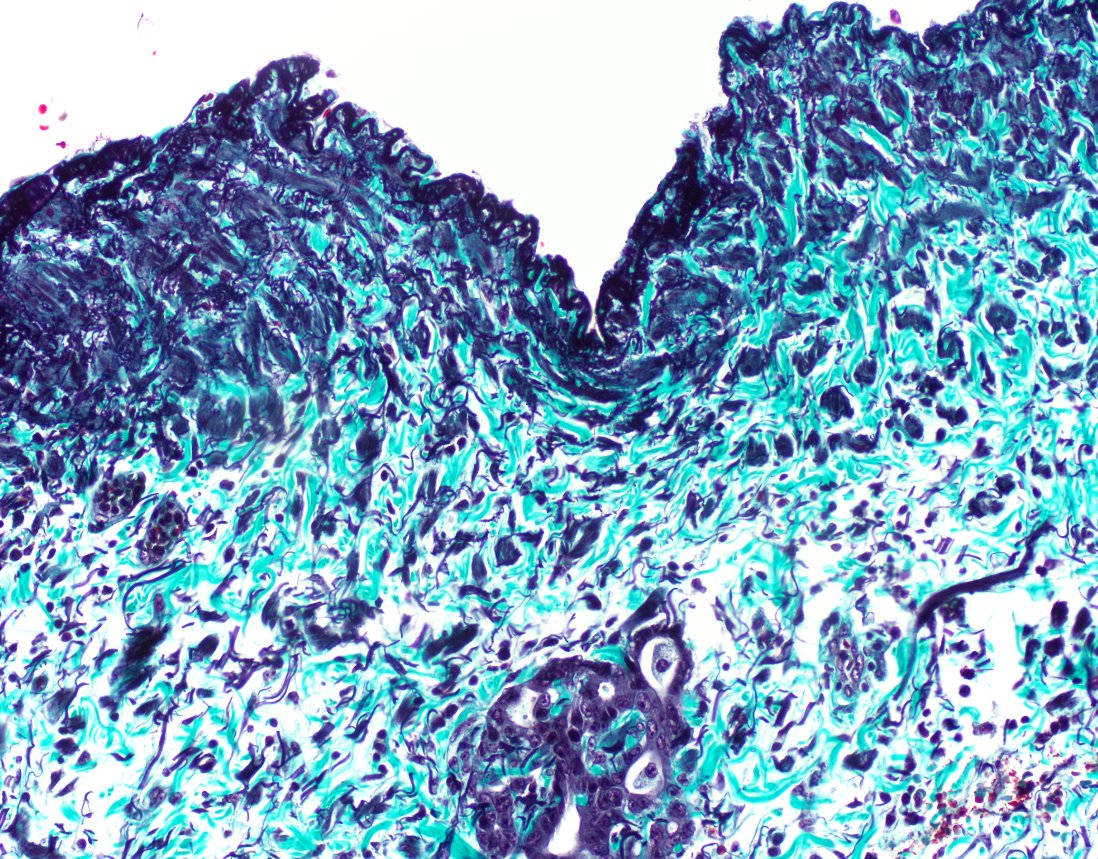

@IHC_guy @stephen_lagana @LiverPath_HPHS @MSeidmanMD @Mvgs1706 @liverpath @RaulSGonzalezMD @PancPathologist @zhang_xuchen @IAbukhiran Definitely vein. Both have an internal layer, only arteries have an external (admittedly attenuated in your photo). Vein adventitia has a ton of smooth muscle bundles and elastic fragments but no organized/condensed external layer. Check out ExpertPath Normal Histology chapters.

Here's an elastichrome (1 image from the uninvolved blood tube and 2 images from involved) . . . both seem to have 1 elastica ... vein and vein???